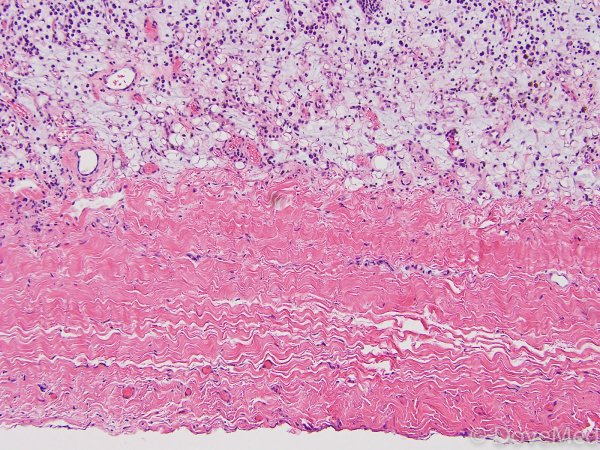

Фибринозный перикардит - это воспалительное заболевание перикарда, оболочки, окружающей сердце. Оно характеризуется образованием в перикарде особой ткани, называемой фибрином, которая может привести к образованию спайков и ограничению движения сердца. Результатом этого процесса является возникновение различных симптомов, таких как боль в груди, одышка, учащенное сердцебиение и слабость. Диагностика фибринозного перикардита включает в себя проведение электрокардиографии, ультразвукового исследования сердца и анализа перикардиальной жидкости. Лечение данного состояния зависит от его тяжести и может включать применение противовоспалительных препаратов, дренирование перикарда или даже хирургическое вмешательство.

Фибринозный перикардит - окраска гематоксилином и эозином